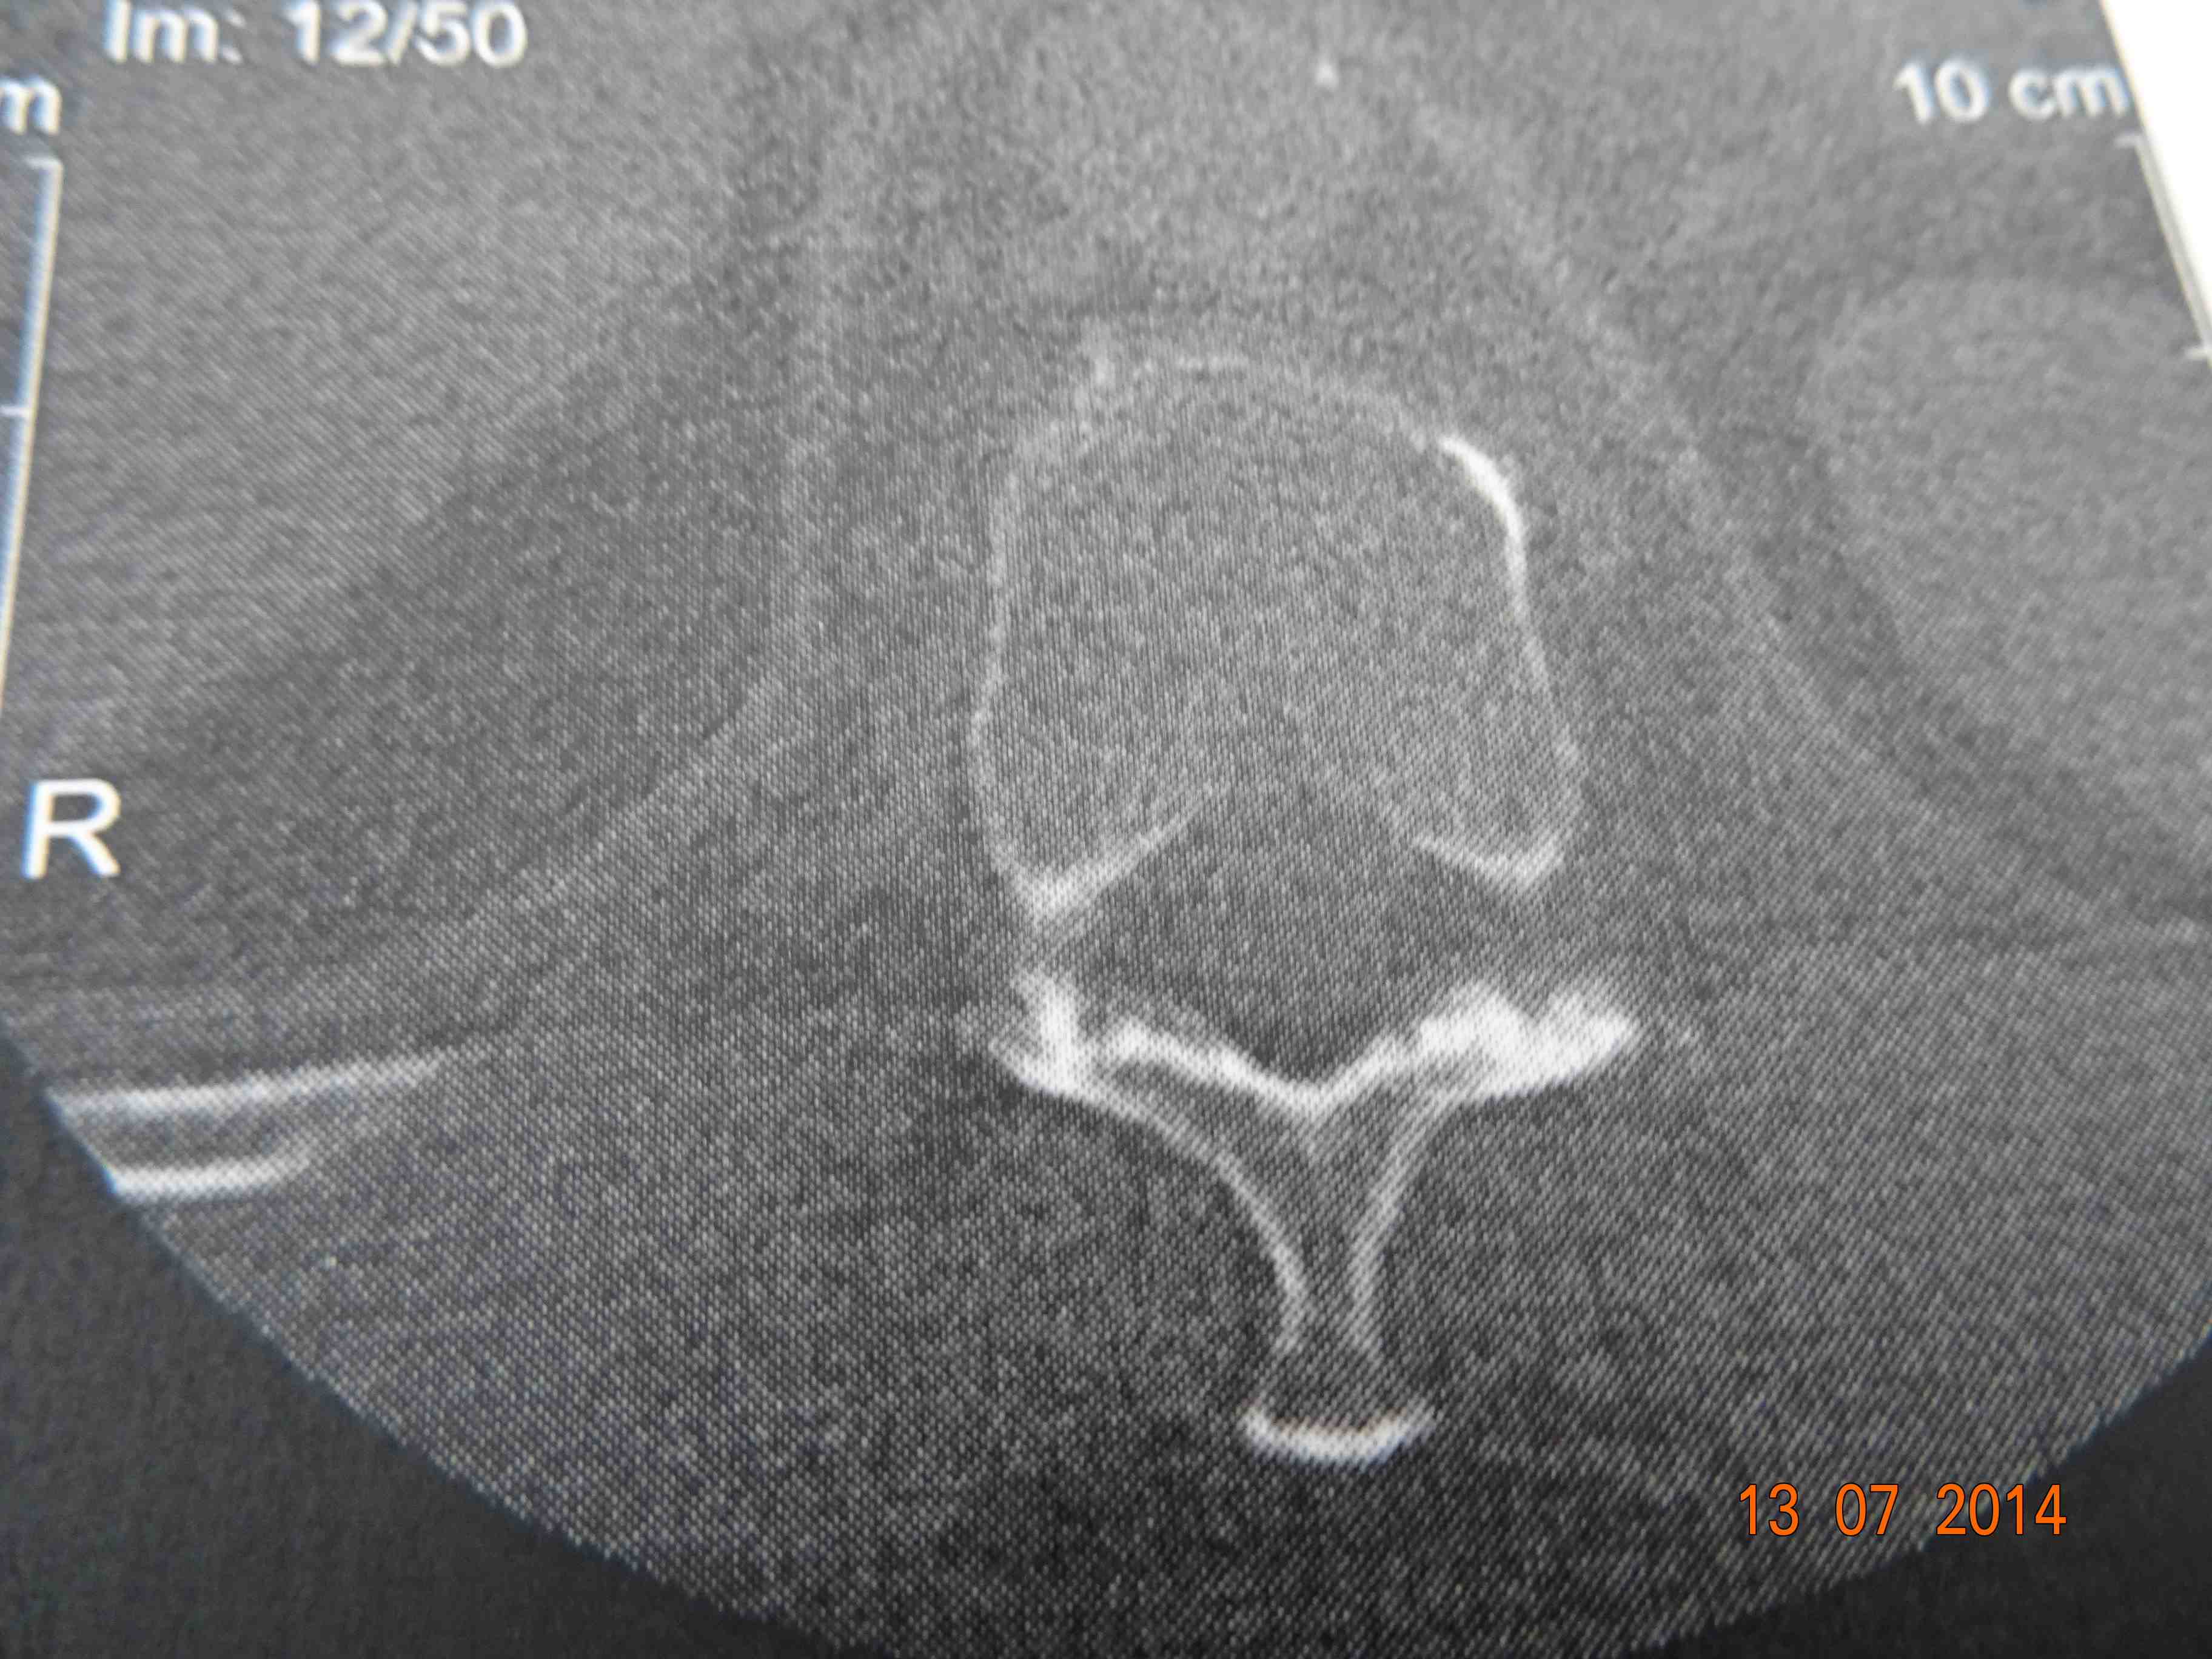

A few weeks ago I had a scan on my back. I'd left the CD with thousands of images of my spine/vertebrae with Camille (my friend and doctor). He gave them back to me at the meet (he is a member of the course committee, owns a horse and is the doctor in charge to attend to fallen jockeys, usually dislocated shoulders). So here is a picture of a good vertebrae and my broken one.

The paper print doesn't show all the pictures on the CD so I've drawn two that illustrate my vertebrae.

This is my fractured vertebrae. These images are photos of the paper printout that came with the CD. On the CD is an image of the other side (not sure if this is from top or bottom). From the other side it looks like 2 ovals separated by a clear gap.